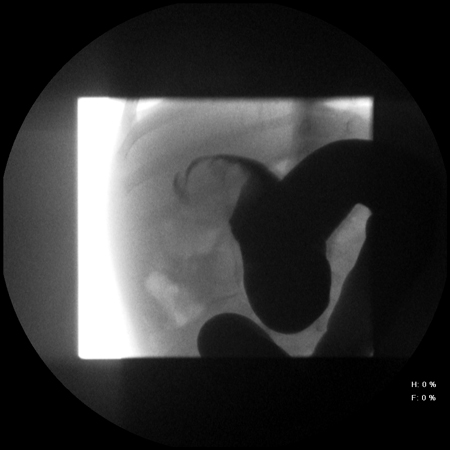

Intussuscepção

Radiografia abdominal que mostra a passagem insuficiente de bário no local da obstrução decorrente da intussuscepção

Do acervo do Dr David J. Hackam; usada com permissão